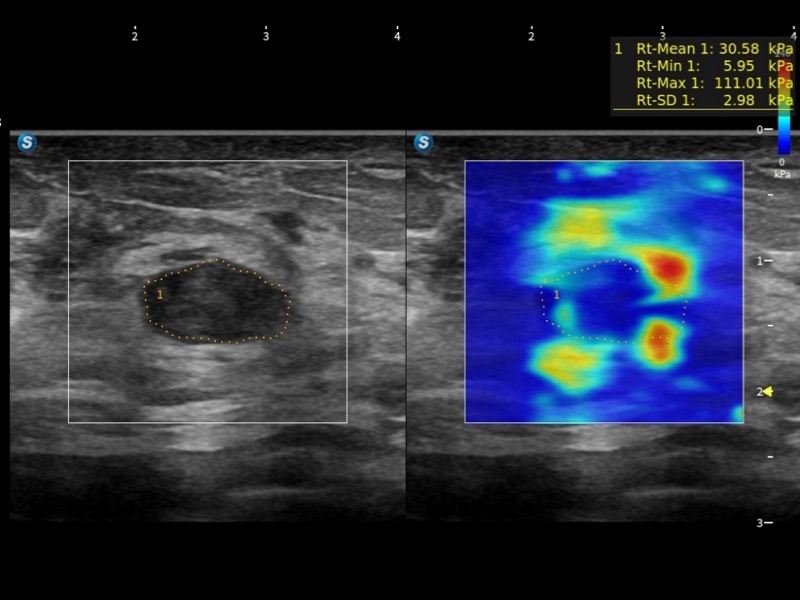

S80 提供多樣化超聲成像技術(shù),可滿足不同科室的需求,在助力掃查診斷和介入治療中發(fā)揮著重要作用。